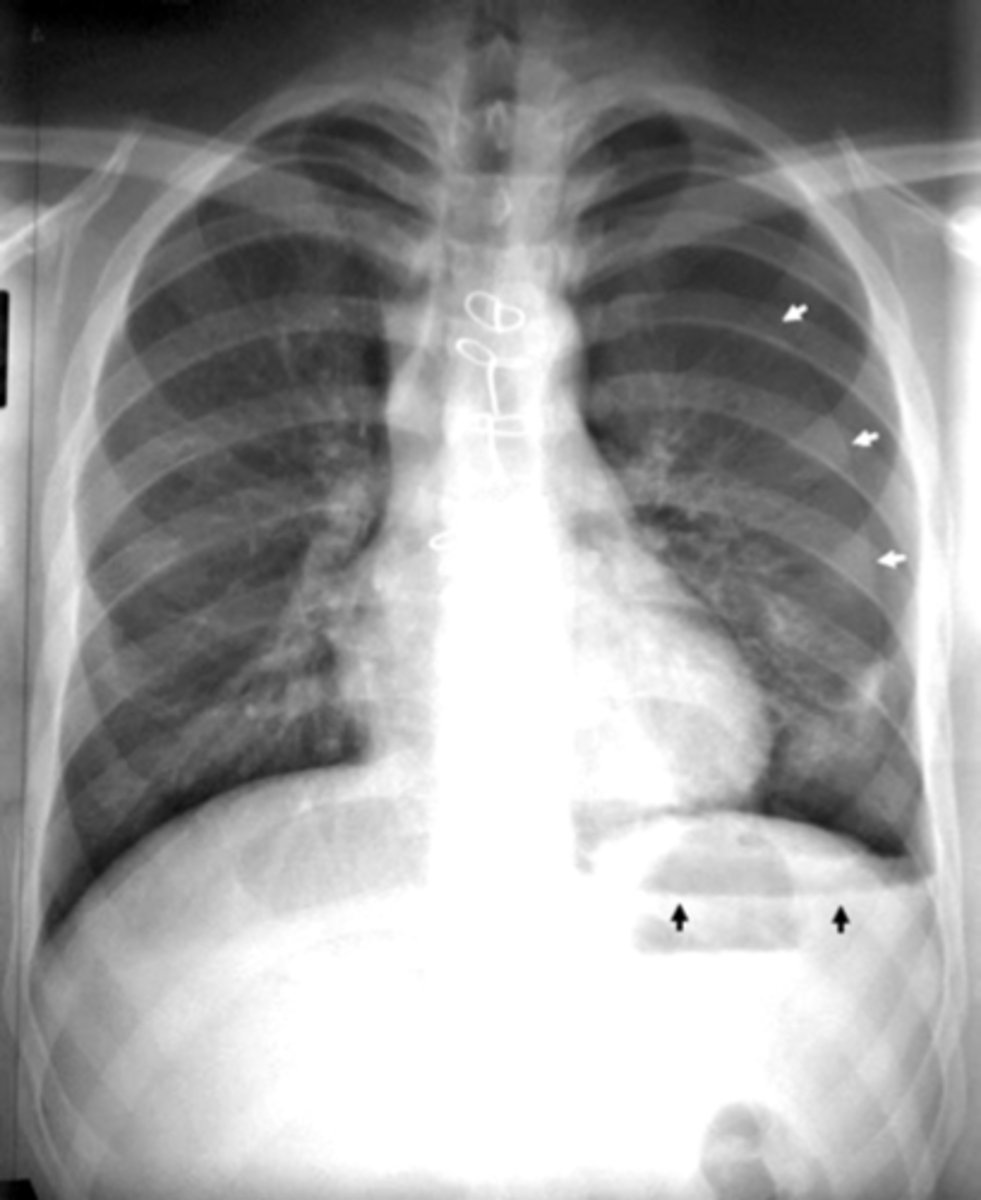

Pleural effusion

Pleural effusion

Pleural effusion (right sided)

congestive heart failure

congestive heart failure

CHF - severe alveolar infiltrate